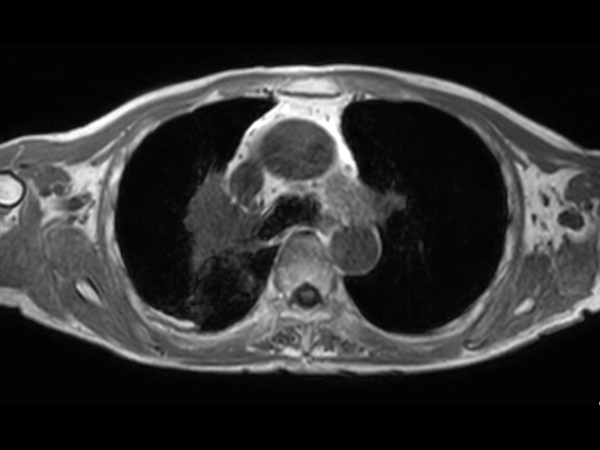

Patient with lung cancer. The ExamCard includes techniques for efficient fat-free imaging over large field-of-views (mDIXON XD), a diffusion procedure with less distortion (DWI TSE XD), a multi-phase contrast-enhanced sequence (4D FreeBreathing) to improve imaging confidence and Compressed SENSE to accelerate the entire exam.

T2w TSE Compressed SENSE

T2w TSE